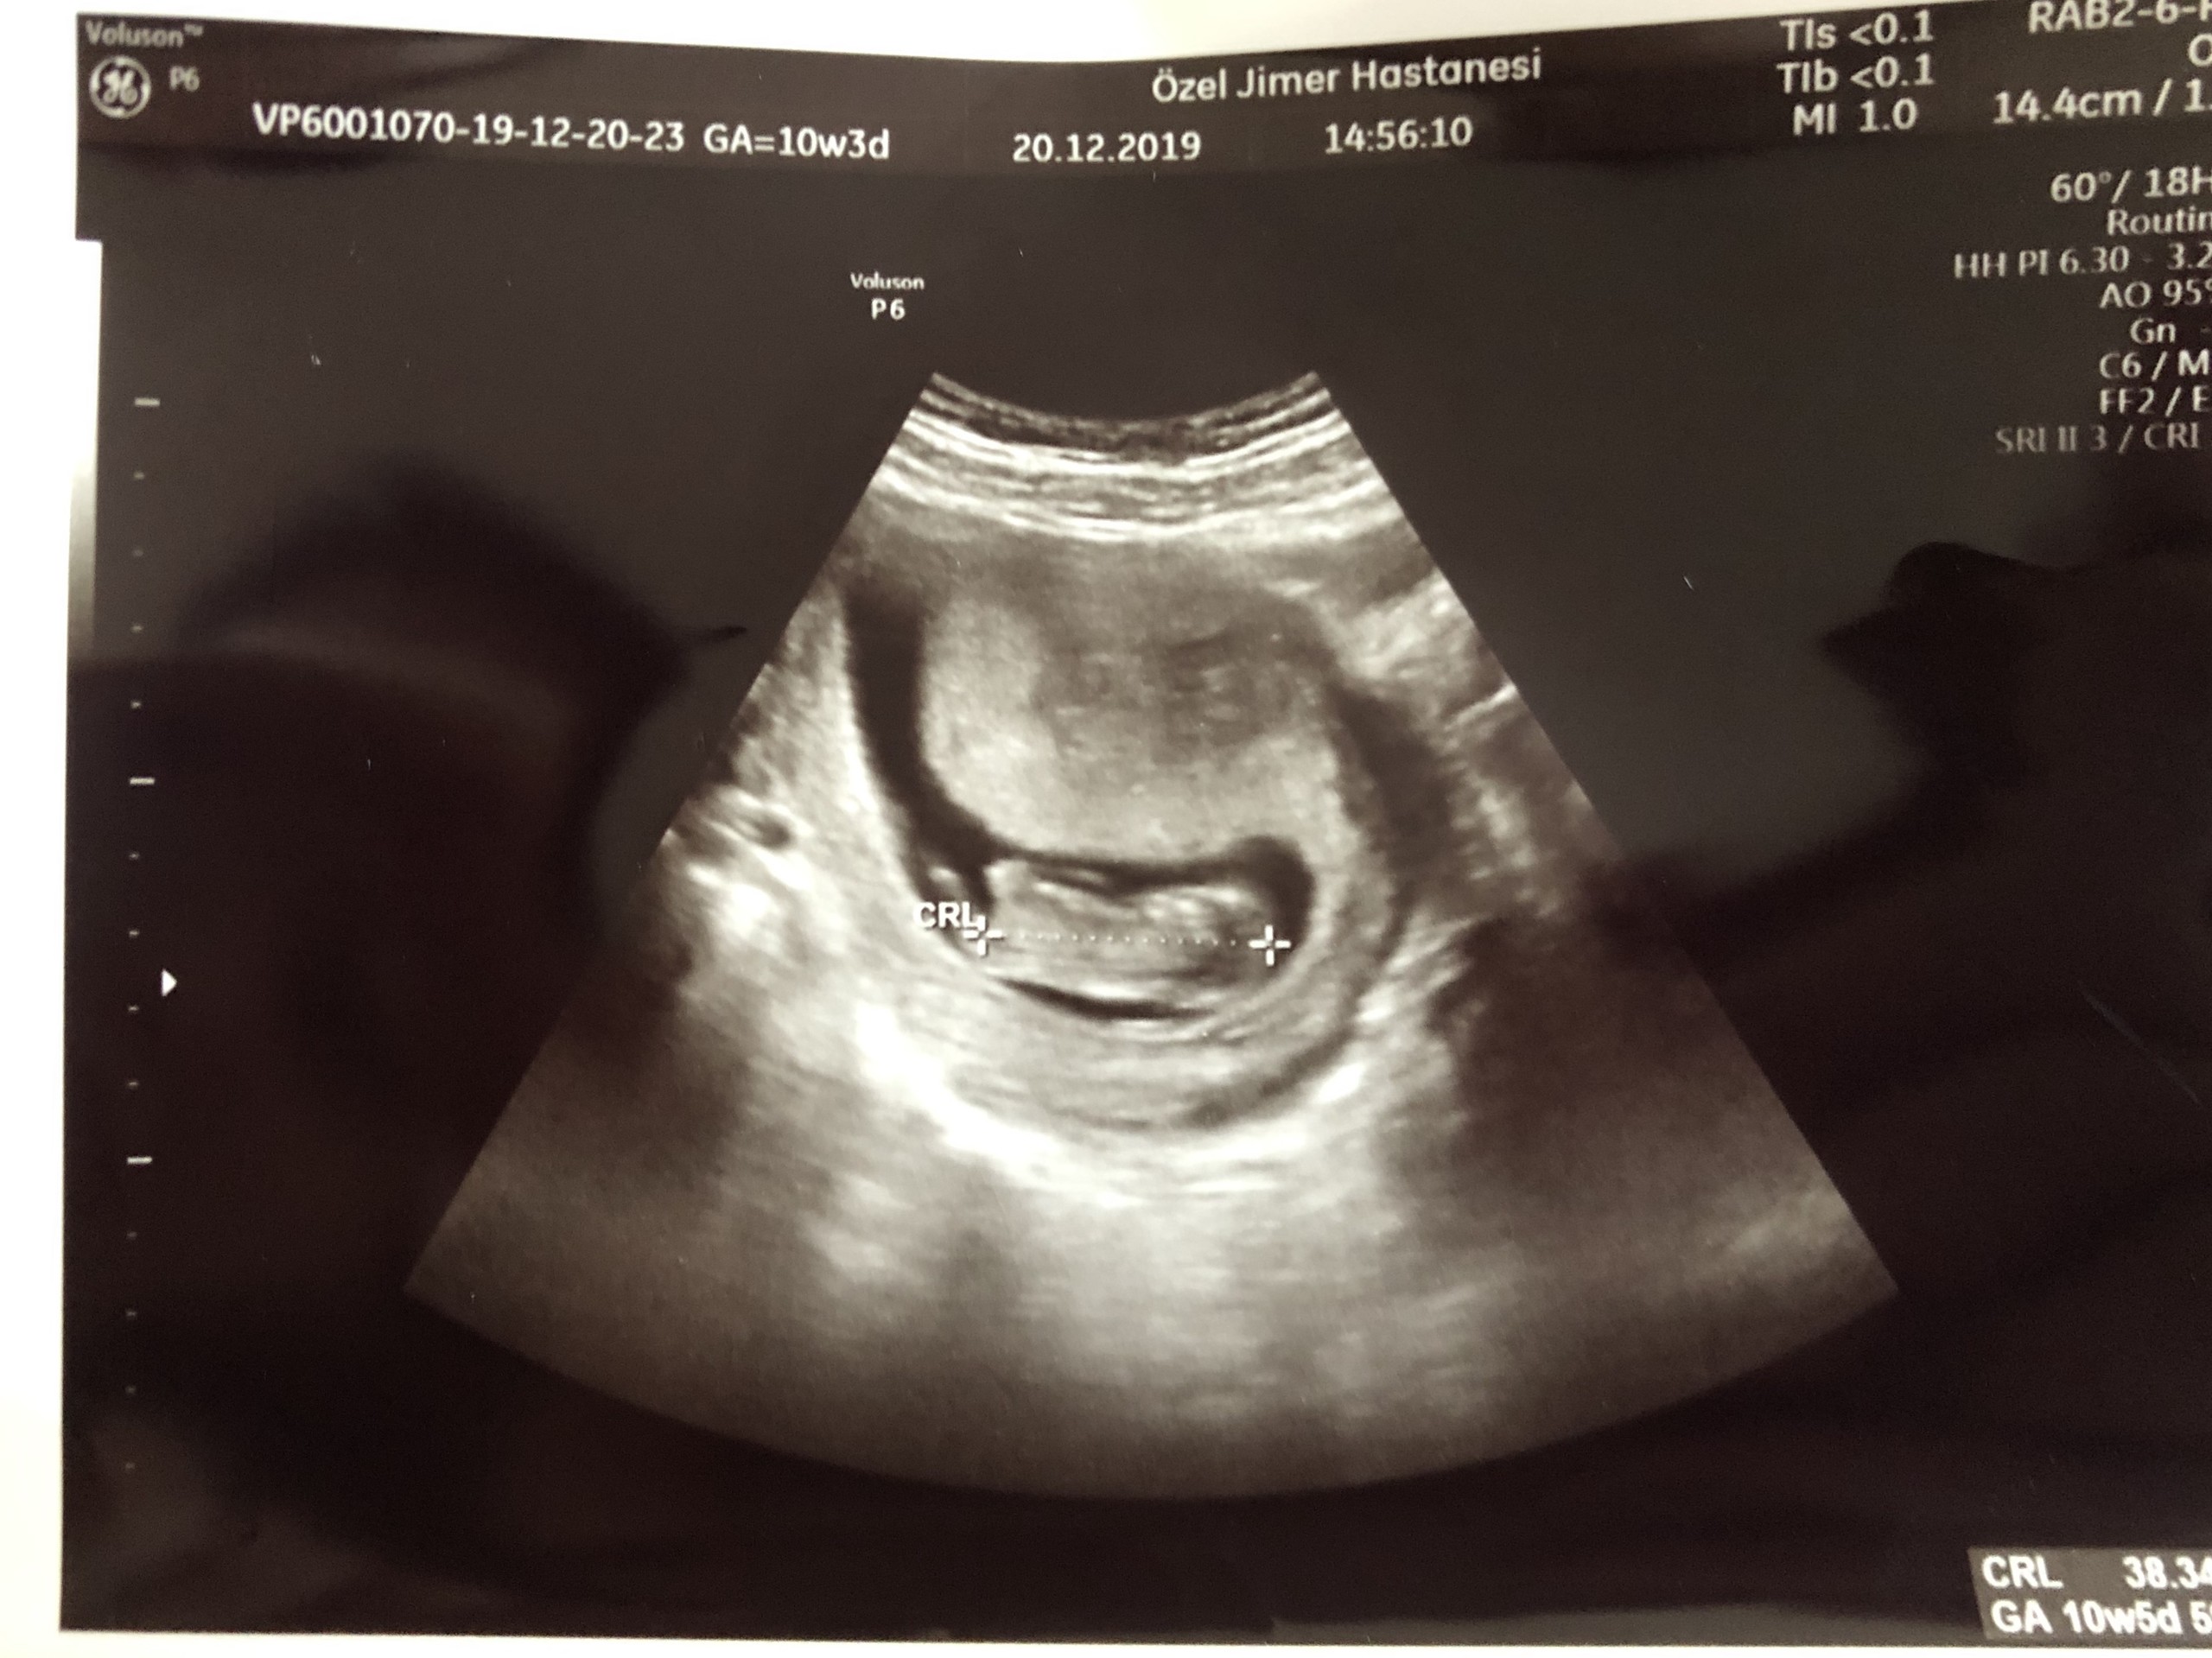

B berivannak Yeni Üye Üye 20 Aralık 2019 #681 malesef başka yok haftaya yenisini alınca atarım inşallah teşekkürler

SadmiN ♥ Evli Mutlu Çocuklu ♥ Yönetici 20 Aralık 2019 #683 Malesef ilgili bölüm çok net değil yanlış bi tahminde de bulunmak istemiyorum cepten yakın çekip gönderebilir misiniz bi kaç tane çekin atın lütfen.

Malesef ilgili bölüm çok net değil yanlış bi tahminde de bulunmak istemiyorum cepten yakın çekip gönderebilir misiniz bi kaç tane çekin atın lütfen.

SadmiN ♥ Evli Mutlu Çocuklu ♥ Yönetici 20 Aralık 2019 #685 Yani çok net olmamakla birlikte erkek diyebileceğimi düşünüyorum.